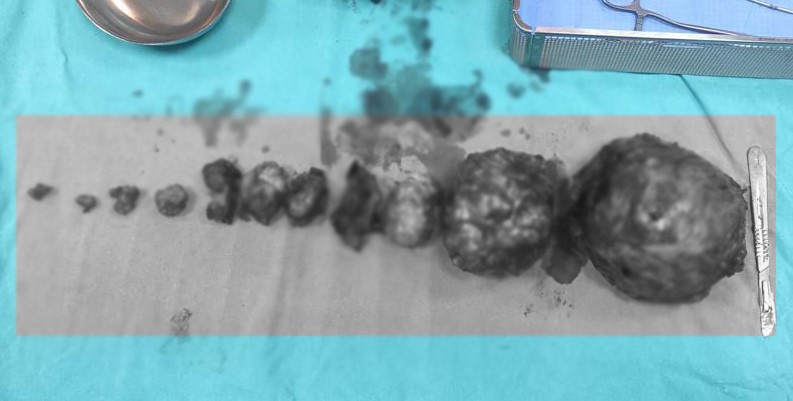

VAN SON HABER - Van’ın merkez İpekyolu ilçesinde yaşayan Hülya Arvas isimli hamile kadının rahminde çok sayıda miyom tespit edildi. Doktorlar tarafından yapılan ilk muayenede, miyomlar nedeniyle bebeğin düşük riski olduğu ve rahminin de alınabileceği değerlendirildi. Van Eğitim ve Araştırma Hastanesinde düşük tehlikesiyle yatan Arvas, 31 haftalık hamileyken doğum sancıları nedeniyle acil bir şekilde ameliyata alındı. Burada Kadın Hastalıkları ve Doğum Uzmanı Dr. Erhan Hanlıgil ve Op. Dr. Ayşe Yavuz tarafından ameliyata alınan anne, 1 kilo 400 gram ağırlığında bir bebek dünyaya getirdi. Daha sonra doktorlar tarafından kadının rahmi alınmadan yaklaşık 5 kilogram ağırlığında 13 adet miyom da başarılı bir şekilde alındı.

Dünyaya gelen ve Muhammed Çınar ismi verilen bebek, 75 gün hastanenin yoğun bakımında izlendikten sonra sağlıklı bir şekilde annesine teslim edildi. Anne Arvas, şu an 6 aylık olan bebeğiyle birlikte operasyonu gerçekleştiren doktorları ziyaret etti. Burada kontrolleri de yapılan anne, alınan miyomlara rağmen rahminin sağlıklı olması nedeniyle yeniden gebelik planlayabilecek.